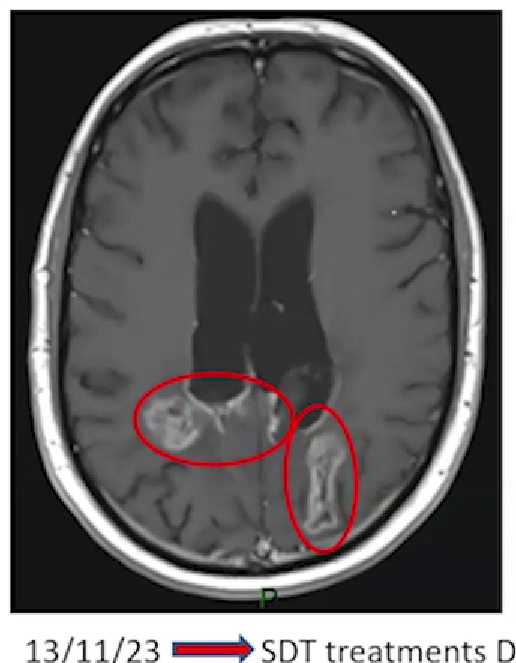

Duncan Campbell's brain scan

Read Duncan's (27 years) full story. Despite being diagnosed with glioblastoma in February 2021, he is living his best life, with a successful career and a fulfilling social life.

Secondary end points of the trial are to assess radiological evidence of cell kill (with MRI scans performed the day after SDT treatment and monthly for three further months), progression free survival and overall survival.